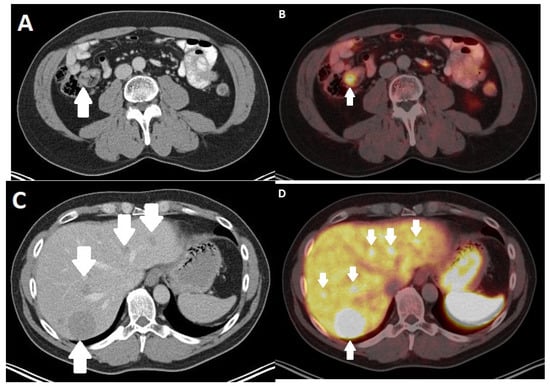

4. Nuclear Medicine Imaging Techniques

- Geijer, H.; Breimer, L.H. Somatostatin receptor PET/CT in neuroendocrine tumours: Update on systematic review and meta-analysis. Eur. J. Nucl. Med. Mol. Imaging 2013, 40, 1770–1780. [Google Scholar] [CrossRef]

- Treglia, G.; Sadeghi, R.; Giovinazzo, F.; Galiandro, F.; Annunziata, S.; Muoio, B.; Kroiss, A.S. PET with Different Radiopharmaceuticals in Neuroendocrine Neoplasms: An Umbrella Review of Published Meta-Analyses. Cancers 2021, 13, 5172. [Google Scholar] [CrossRef]

- Yoo, J.; Kim, S.H.; Jeon, S.K.; Bae, J.S.; Han, J.K. Added value of [(68)Ga]Ga-DOTA-TOC PET/CT for characterizing pancreatic neuroendocrine neoplasms: A comparison with contrast-enhanced CT and/or MRI in a large study cohort. Eur. Radiol. 2021, 31, 7734–7745. [Google Scholar] [CrossRef]

- Sadowski, S.M.; Neychev, V.; Millo, C.; Shih, J.; Nilubol, N.; Herscovitch, P.; Pacak, K.; Marx, S.J.; Kebebew, E. Prospective Study of 68Ga-DOTATATE Positron Emission Tomography/Computed Tomography for Detecting Gastro-Entero-Pancreatic Neuroendocrine Tumors and Unknown Primary Sites. J. Clin. Oncol. Off. J. Am. Soc. Clin. Oncol. 2016, 34, 588–596. [Google Scholar] [CrossRef]